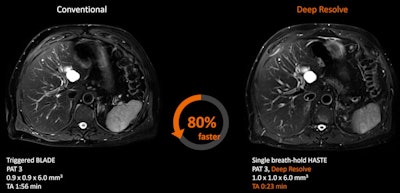

Deep Resolve Boost, a k-space-based reconstruction protocol that focuses on artifact reduction, is a recent addition to the Deep Resolve AI-based reconstruction protocol for MRI introduced at RSNA 2020.

Looking further ahead, the plan is to add capabilities for diffusion-weighted imaging (DWI) and fast T2-weighted imaging in the abdomen (HASTE).

"DWI can provide critical information about the cellularity of tissue but is also typically a long examination," the vendor noted. "Neurological and oncological imaging will certainly benefit. Fast T2-weighted imaging is particularly useful in abdominal imaging for oncology questions. Multiple (usually three) breath-holds are required. With Deep Resolve, only one breath-hold is needed, making this exam easier for patients."

Depending on the body region and measurement, the software can save up to 88% of scan time but also reduce energy consumption by 60%, it claimed. "Every bit of energy that you can save in MRI helps reduce the environmental impact.